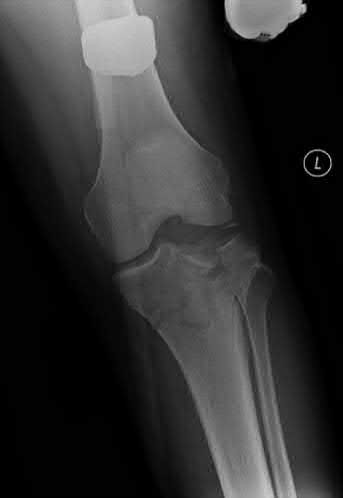

A 36-year-old male falls from a 10-ft scaffold and suffers the injuries shown in Figures A and B. The patient is placed in a spanning external fixator and brought back to the operating room once his soft tissues are amenable. Planning to use a dual-incision approach, what is the correct interval to use when approaching the medial side?

The posteromedial approach to the tibial plateau is between the the pes anserine tendons and the medial head of the gastrocnemius.

A dual-incision approach is often utilized to optimally place definitive fixation for bicondylar tibial plateau fractures. For fractures that require posterior or posteromedial fixation, the correct interval is between the pes anserine and the medial head of the gastrocnemius.

Figure A and B exhibit a bicondylar tibial plateau fracture with a posteromedial fragment noted on the lateral x-ray. Illustration A exhibits the surrounding anatomy and interval in between the medial head of the gastrocnemius and the pes anserine.